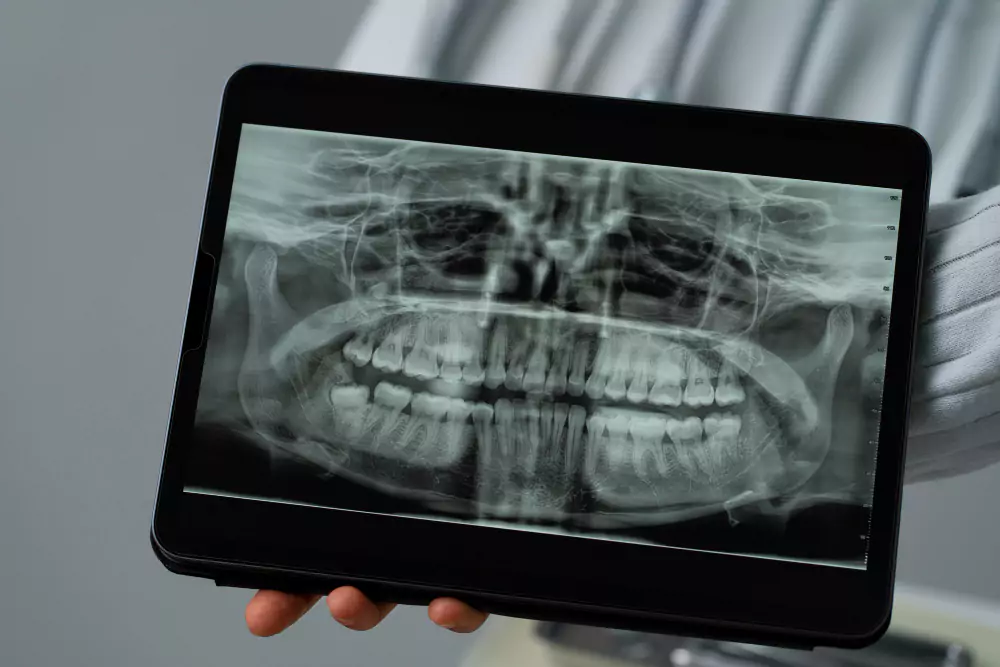

Comprehensive Examination – Assessment of teeth, gums, bite, and jaw using advanced diagnostic tools like digital X-rays and intraoral scanning.

Comprehensive Evaluation – Our team conducts a detailed oral examination, including X-rays and bite analysis, to assess the condition of teeth, gums, and jaw.

Detailed Examination – X-rays and evaluation to plan the safest approach

Accurate diagnosis is the foundation of effective dental care. At Elite Dental Care and Aesthetics, we use Digital X-Rays, a modern and safe imaging technology that helps us see beyond the surface of your teeth and gums. Unlike traditional X-rays, digital radiography offers clearer, high-resolution images instantly on screen, allowing for precise diagnosis and better treatment planning.

Digital X-rays emit significantly less radiation, making them safer for children and adults. They are also faster, more comfortable, and environmentally friendly since they don’t require film or chemical processing.

Why Digital X-Rays?

Provide detailed images of teeth, roots, and jawbone

Detect cavities, infections, and hidden dental issues early

Monitor tooth development in children

Help in planning orthodontic, implant, and cosmetic treatments

Allow easy storage and sharing for ongoing care

Benefits of Digital X-Rays

Safe & Low Radiation – Up to 90% less radiation exposure than traditional X-rays

Instant Results – Images appear immediately on the screen

Better Accuracy – High-resolution imaging for precise diagnosis

Comfortable & Quick – Hassle-free process, especially for kids and anxious patients

Eco-Friendly – No films or harmful chemicals required

Digital X-rays are essential for preventive care as they help detect problems before they become painful or complicated. Whether it’s identifying cavities between teeth, assessing wisdom tooth position, or planning advanced procedures like implants and orthodontics, our digital imaging system ensures every detail is considered.

At Elite Dental Care and Aesthetics, your safety and comfort come first. With digital X-rays, we combine advanced technology with compassionate care, ensuring you receive accurate, efficient, and stress-free dental treatment.